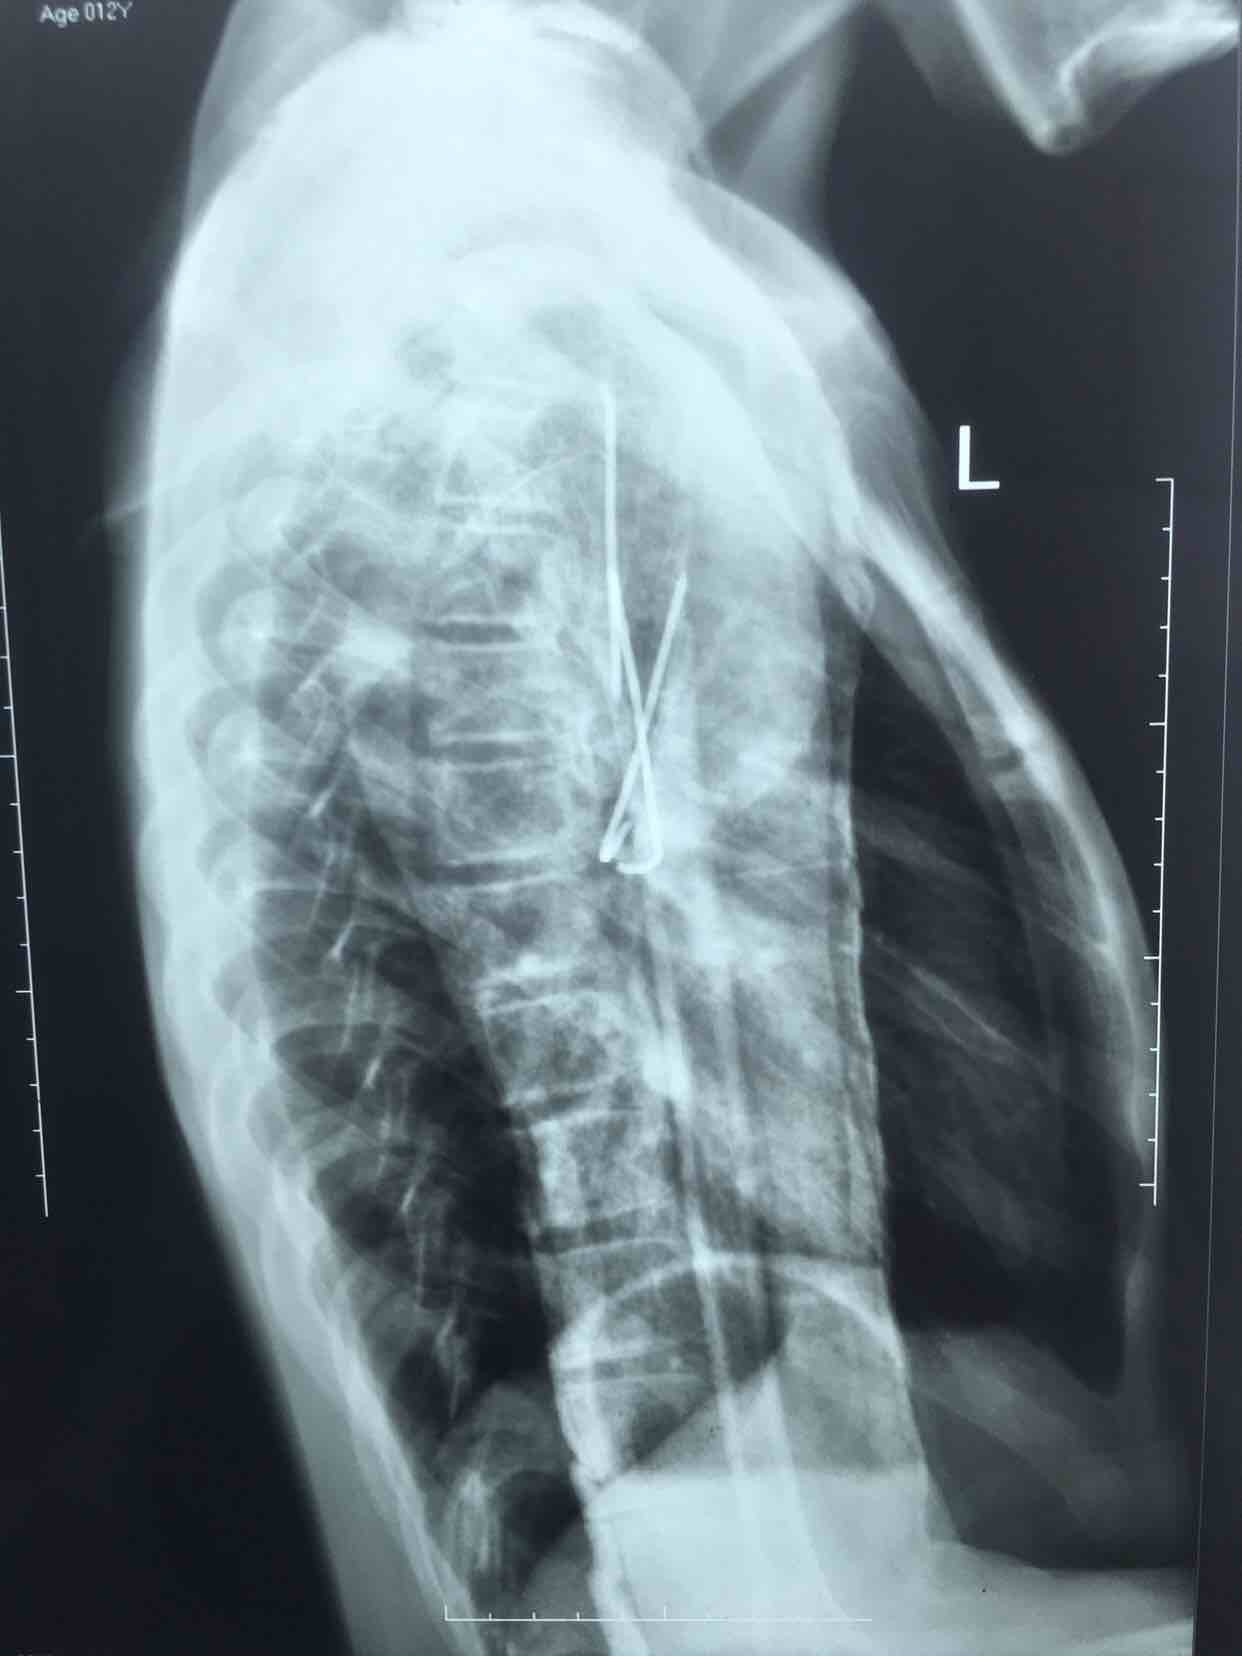

诊断 处理

在臂丛麻醉下行闭合复位内固定术,术后过肩石膏托固定,抗炎,消肿等处理。